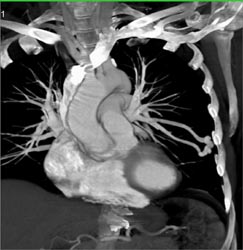

Hydropneumothorax